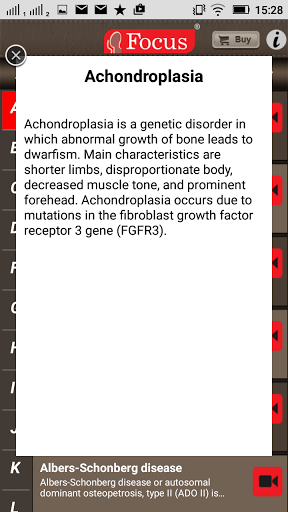

The FOCUS Animated Pocket Dictionary of RHEUMATOLOGY is the first ever animated dictionary in the subject. A valuable reference for physicians and students alike, it covers 100 rheumatology related terms and definitions. All the definitions have been graphically described with the help of 3D animations and are accompanied by text definitions.

The Focus Animated Pocket Dictionaries are the world’s first ever animated dictionaries that provide definitions of medical terms with the aid of realistic and narrated 3D animations, complimented with text definitions. Terms arranged alphabetically making definitions easy to search. These unique visual dictionaries are excellent reference sources for health professionals, students and health consumers. The videos play independent of the internet once downloaded.